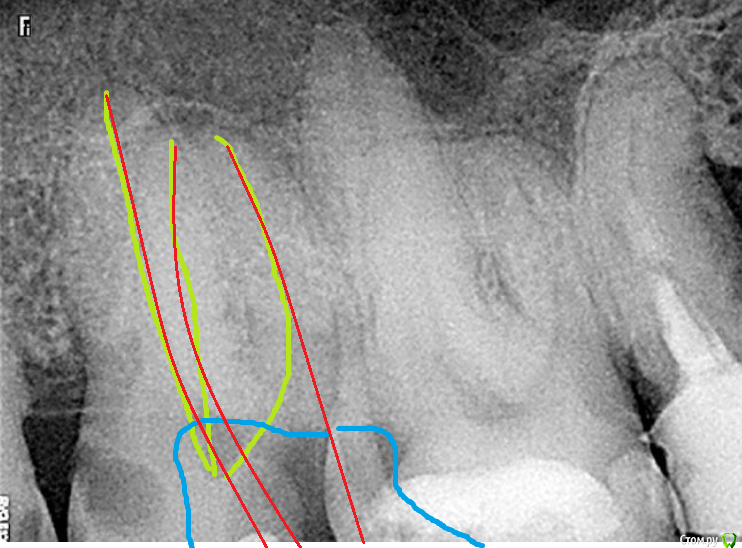

Fred Опубликовано 8 февраля, 2016 Поделиться Опубликовано 8 февраля, 2016 Говорите что хотите, но есть зубы, которые приходится удалять из-за доступа. Только что был вот такой пациент от другого врача, который решил, что я как-то смогу пролезть в его верхний второй моляр. Я сделал несколько снимков с зеркалом для ориентира (диаметр зеркала - 14 мм). Между вторыми молярами примерно половина этого расстояния. Головка наконечника не лезет, кламмер не одевается, так как упирается в антагонисты, файлами может и можно было бы попасть в небный и ДБ при их идеальном направлении в сторону открытого просвета рта. О МБ/МБ2 речь и не идет. Как вообще лечить банальные кариесы такому человеку, у него все моляры требуют вмешательства?Кто как решал бы проблему? http://s29.postimg.org/525xdo3jb/Untitled_6.jpg 1 Ссылка на комментарий

Fred Опубликовано 8 февраля, 2016 Автор Поделиться Опубликовано 8 февраля, 2016 Странная тема. Особенно если учесть что 6 дистально разрушен и мы имеем полное моральное право его чуть убрать. Меняем ангуляцию доступа. Транспортируем устье и устьевую треть МБ, МБ2. Берем короткие файлы и спокойно работаем. Хотел бы увидеть, как тут спокойно работать, да хоть на рисунуке. Как их туда "спокойно" просунуть? http://s27.postimg.org/qxfmq981f/Untitled_6.jpg Ссылка на комментарий

DmitrySH Опубликовано 8 февраля, 2016 Поделиться Опубликовано 8 февраля, 2016 Когда все лишнее убрать, то до устья уже в два раза больше дистанция. Доступ медиально-щечно в небный, медиально -небно в щечные. Ссылка на комментарий

Fred Опубликовано 8 февраля, 2016 Автор Поделиться Опубликовано 8 февраля, 2016 Когда все лишнее убрать, то до устья уже в два раза больше дистанция. Доступ медиально-щечно в небный, медиально -небно в щечные.Да, будет больше, согласен, миллиметра на 3-4. Только чем все это убрать, я не могу наконечник туда засунуть даже без бора... Ссылка на комментарий